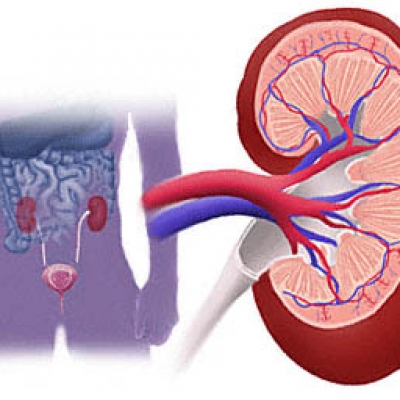

Vesekõ-betegség érendje